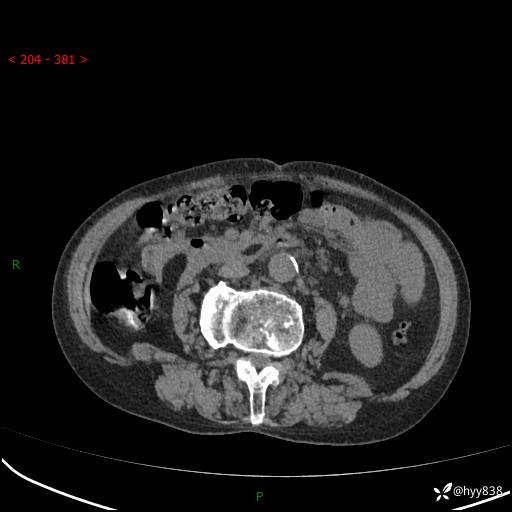

全腹部CT平扫